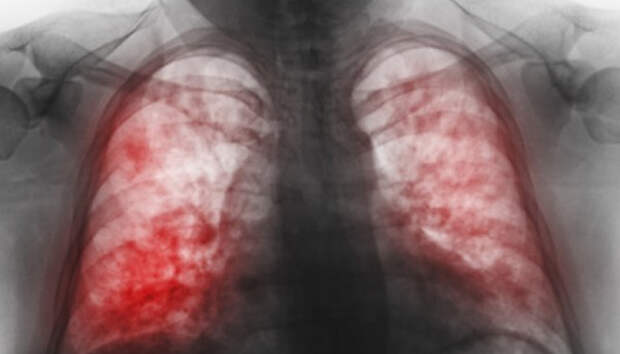

Всем пациентам с воспалением легких неоднократно проводится исследование на COVID-19 Двенадцать человек за сутки госпитализированы с внебольничной пневмонией в Карелии, сообщает оперштаб по борьбе с распространением коронавирусной инфекции. Летальных исходов не зарегистрировано. Начиная с 1 апреля, с внебольничной пневмонией госпитализирован 931 пациент, 65 человек умерли (с учетом пациентов, госпитализированных ранее указанного периода).